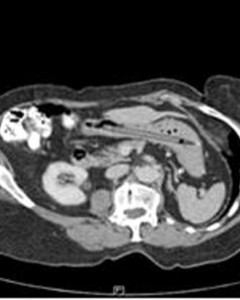

A CT scan of a 76-year-old woman's stomach shows the outline of a pen that was lodged there for 25 years. Photo: BMJ.com

A 76-year-old British woman recently checked herself into a hospital in England with complaints of diarrhea and weight loss. When doctors examined her, they found an unrelated problem: A felt-tipped pen that had been stuck in her stomach for 25 years. The patient recalled having used the blunt end of the pen to "inspect a spot on her tonsils when she slipped, fell, and accidentally swallowed the pen," says ABC News. The pen had never caused her any problems, despite being in her stomach for more than two decades. When the team of doctors "fished the pen out of its gastrointestinal hiding place, they found that it still wrote clearly." Here, five other strange objects found in the stomachs of patients across the globe: